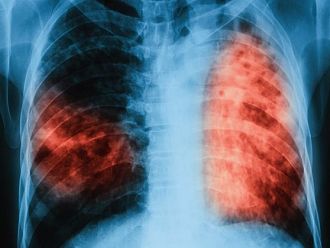

За втори път през 2019 г. ще се проведат безплатни прегледи за туберкулоза в лечебни заведения за диагностика и лечение на туберкулозата в страната, съобщиха от здравното ведомство.

По време на „Седмицата на отворените врати“ на всеки желаещ се предлага скрининг за риска от туберкулоза чрез анкета и консултации. На лицата, които са в риск, се провеждат допълнителни прегледи и изследвания. При откриването на случаи на туберкулоза своевременно се предприемат мерки за хоспитализация и лечение, в резултат на което се прекъсва веригата за предаване на инфекцията.

По време на проведената през месец март 2019 г. кампания анкетирани за туберкулоза са 2 952 лица, а на 1 792 в риск от туберкулоза са извършени медицински прегледи и допълнителни изследвания. Открити са 24 лица с туберкулоза и 82 лица с латентна туберкулозна инфекция, на които е започнато лечение.

Инициативата се провежда от 2009 г. и е допринесла за по-добра разкриваемост на случаите на туберкулоза и латентна туберкулозна инфекция, ефективна превенция на туберкулозата в страната и осигуряване на достъп до здравни грижи. По време на проведените за периода 2009 г. – 2018 г. „Седмици на отворени врати” анкетирани за туберкулоза са 114 730 лица, открити и насочени за лечение са 1 242 лица с туберкулоза, открити с латентна туберкулозна инфекция и обхванати с химиопрофилактика са 4 351 души.